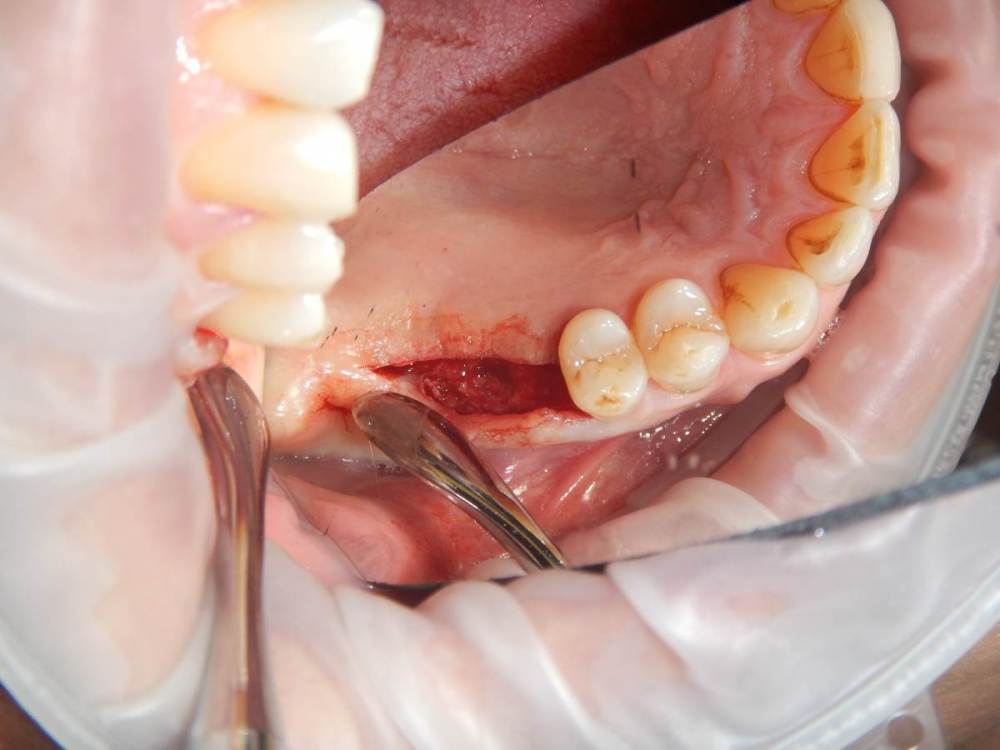

annda Опубликовано 11 июня, 2021 Поделиться Опубликовано 11 июня, 2021 (изменено) Ничего не беспокоит.Зубы удалены лет 15 назад Изменено 11 июня, 2021 пользователем annda 1 Ссылка на комментарий

Карен Аванесов Опубликовано 11 июня, 2021 Поделиться Опубликовано 11 июня, 2021 Анна здравствуйте. Версий много, вскрытие покажет, главное нет признаков воспаление, в любом случае интересный клинический случай под минимальное вмешательство, обязательно покажите развязку. 1 Ссылка на комментарий

Astronaft Опубликовано 11 июня, 2021 Поделиться Опубликовано 11 июня, 2021 Радиография была один в один с вашим случаем. Результат биопсии: рецидуальная киста с кристаллами холестерина. Но конечно может быть что-нибудь другое. 4 Ссылка на комментарий

annda Опубликовано 12 июня, 2021 Автор Поделиться Опубликовано 12 июня, 2021 (изменено) Спасибо всем. Вмешательства не было, кроме удаления. Я так понимаю, тактика заключается в доступе и банально кюретаже? Графт по убеждениям, дефект все одно получается практически четырехстеночный... Главное, не наджабить кортикалку ГП. Я так понимаю, процесс все же из пазухи, был с зубами связан? Изменено 12 июня, 2021 пользователем annda Ссылка на комментарий

Astronaft Опубликовано 12 июня, 2021 Поделиться Опубликовано 12 июня, 2021 (изменено) В моем случае процесс одонтогенный. Киста это остаток после удаления зуба. В вашем случае не должен быть из пазухи. Да - там есть истончение кортикальной пластины в одном месте, но вроде как без инвагинации. Границы везде четкие, т.е. процесс доброкачественный. Из пазухи в кость можно проникнуть только инвазивно. Лизис, а не раздвигание. Карцинома - границы были бы другие. Т.е. процесс либо происходит из самой кости, или одонтогенный. Изменено 12 июня, 2021 пользователем Astronaft 1 Ссылка на комментарий